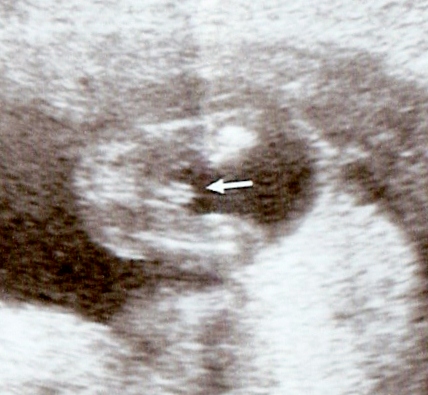

Ok, had a quick scan at 15w0d to peek at gender. She first said girl for a while, then changed her mind half way through the scan. I see its obviously protruding, but the 3 lines are making me crazy! What do you think? :suprise:

Attachment 8634Attachment 8635Attachment 8636